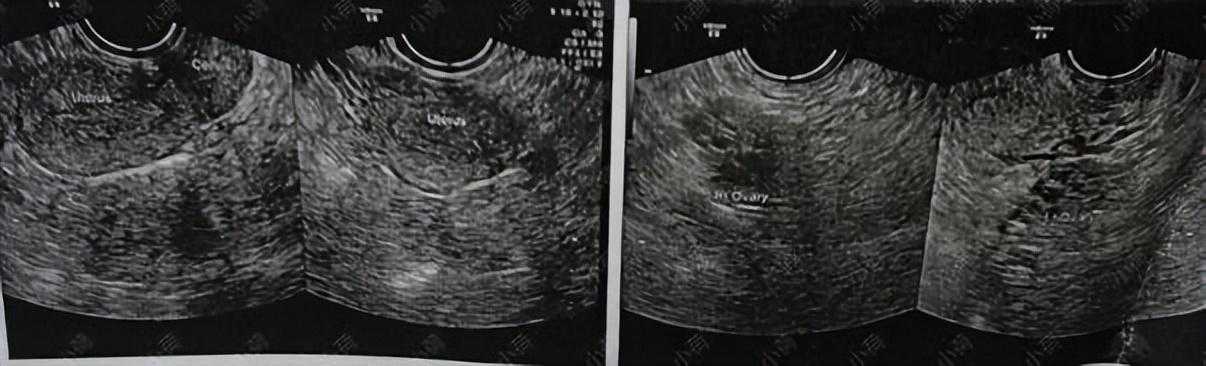

了解她的情况之后我让她去化验血,检查一下激素六项+β人绒毛膜促性腺激素,以排除怀孕;再做一个经阴道B超。

结果显示:多囊卵巢综合征,激素紊乱。